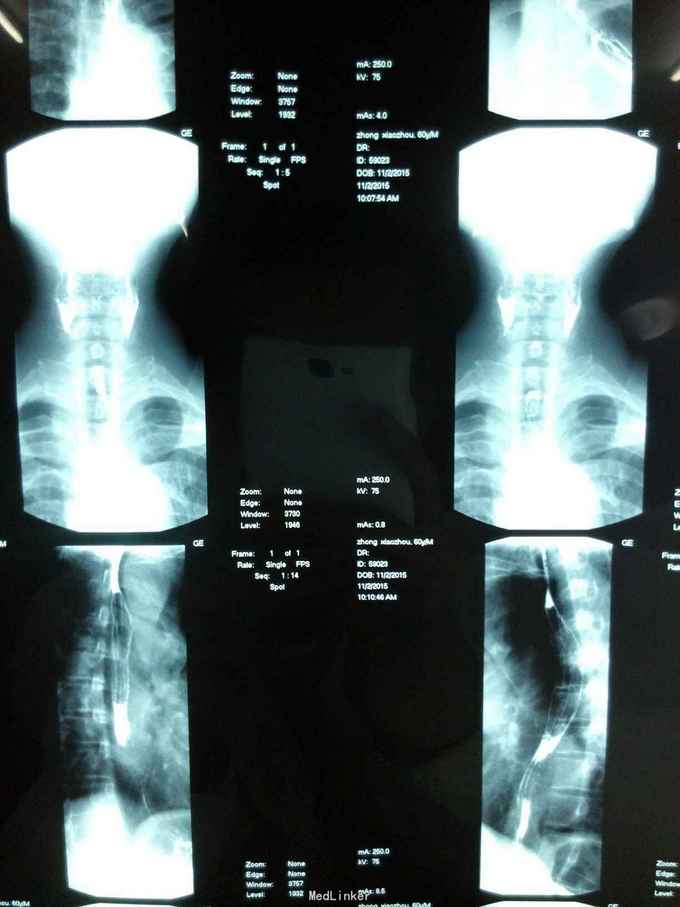

患者男,60岁,因“声音嘶哑一年余入院”。入院后诊断为:喉癌

查体:心肺腹未见异常;右侧声带前段、前联合见菜花样新生物,表面欠光滑,闭合时见少于裂缝。 辅查:病理活检、颈部增强肺部平扫CT、电子鼻咽喉镜、肺功能、食道吞钡、消化泌尿系统彩超。如图

诊断:喉癌 治疗:手术方式:喉额侧垂直部分切除+钛网支架喉功能重建+气管切开术

术后病理:高分化磷状细胞癌,切缘未见癌累及。 术后患者恢复较快,一周后试进流质饮食,试进食无明显异常后2天拔胃管。术后12天拔管。切口愈合良好,未见明显红肿,钛网在位无外露。 钛网喉功能重建为近年来新型手术方式,手术优势在于创伤小,恢复快,术后再造通气管道,防止狭窄! 国内由中山大学附属肿瘤医院刘学奎教授最先应用!#^_^#